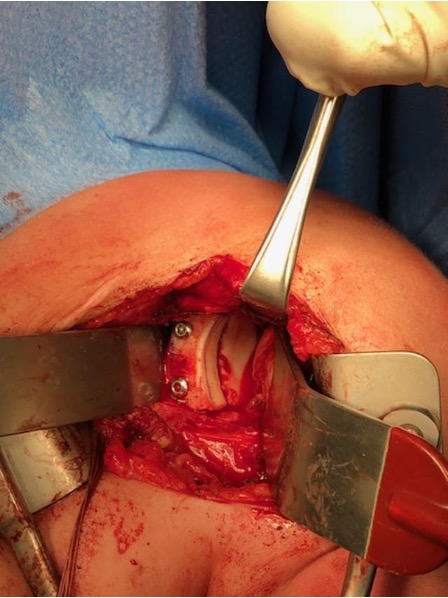

Case 1: Failed Latarjet